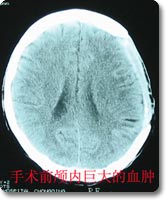

神经外科治疗各种颅脑损伤病人已有50余年历史,拥有一支高素质的专业医护队伍,先后收治各类颅脑损伤病人7000余例,尤其是在严重颅脑损伤的抢救方面,已总结出一整套抢救治疗方案,积累了丰富的救治经验,救治成功率高于文献报导的平均水平,死亡率、残废率低。 |